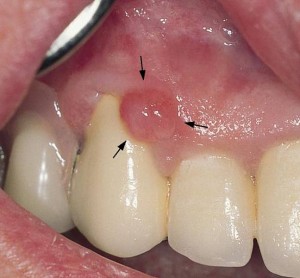

Клиническая картина и диагноз. Для фиброматоза характерны бугристые разрастания слизистой оболочки десны по всему альвеолярному отростку. Течение заболевания медленное, прогрессирующее. Разрастания безболезненные, вид слизистой оболочки не изменен. На рентгенограмме костная ткань, как правило, без изменений, возможен незначительный остеопороз. Эпулис характеризуется разрастанием десны, чаще межзубного сосочка на ограниченном участке. С точки зрения патологической картины могут быть фиброзные, сосудистые и гигантоклеточные эпулисы. На рентгенограмме определяется очаговый остеопороз межзубной альвеолярной перегородки.